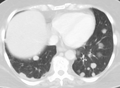

صورة أشعة مقطعية لانبثاث في الرئة